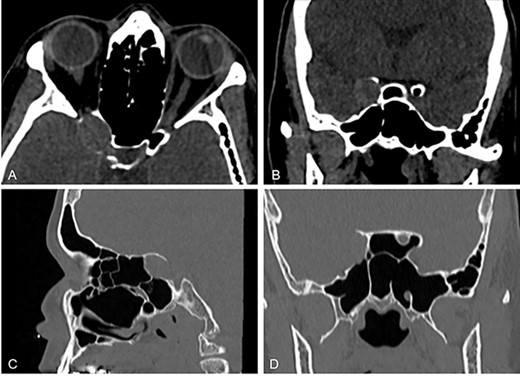

A pre-surgical paranasal sinus CT scan showed bilateral pneumatization of ACP; the right one had thin eroded bony walls and was occupied by a soft tissue density lesion that compressed the orbital apex (Fig. 2).

Paranasal sinus CT scans multiplanar reconstructions in axial (A), coronal (B, D) and sagittal (C) planes, with modified window (A and B) and bone algorithm (C and D); they show the right ACP with thin eroded walls, occupied by an oblong, soft tissue density mass that expands the bone cortical and compresses the right orbital apex.